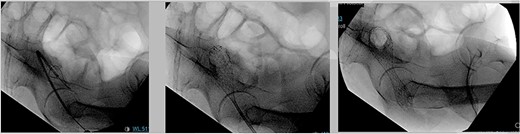

After extensive discussion and education with the patient in regard to surgical options, such as diverting transverse colostomy or endoscopic decompressive stent placement, the patient decided to undergo colonic stent decompression. During hospital Day 4, a 2.5 cm × 9.0 cm colonic stent was deployed, we were only able to deploy it just above the anorectal ring (Fig. 5), with brisk colonic decompression. During postoperative day (POD) 1, she had voluminous fecal incontinence for 12 hours before spontaneous resolution. Prior to discharge, a contrast enema demonstrated stent patency and excluded synchronous lesions. Patient was having liquid bowel movements and was tolerating a diet. Prior discharge a med-port was inserted for chemotherapy. Patient was successfully discharged on POD 2.

Endoscopic 2.5 cm × 9 cm. Wall flex low rectal stent placement under fluoroscopy guidance.